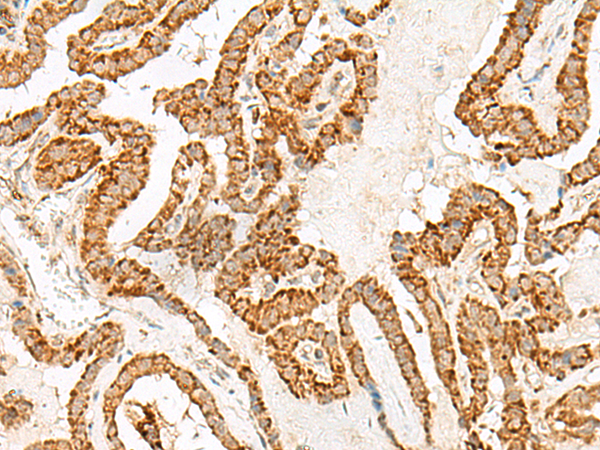

分类: 科研抗体货号: P06594别名: GT01; PGR4; BMIQ10; GPR120; GPR129; O3FAR1应用: IHC反应种属: Human